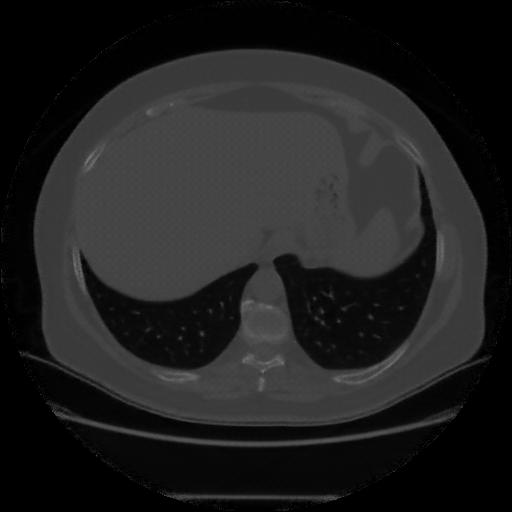

Original VENOUS CT scan

Lung window (WL -600, WW 1500 β†’ Low βˆ’1350, High +150)